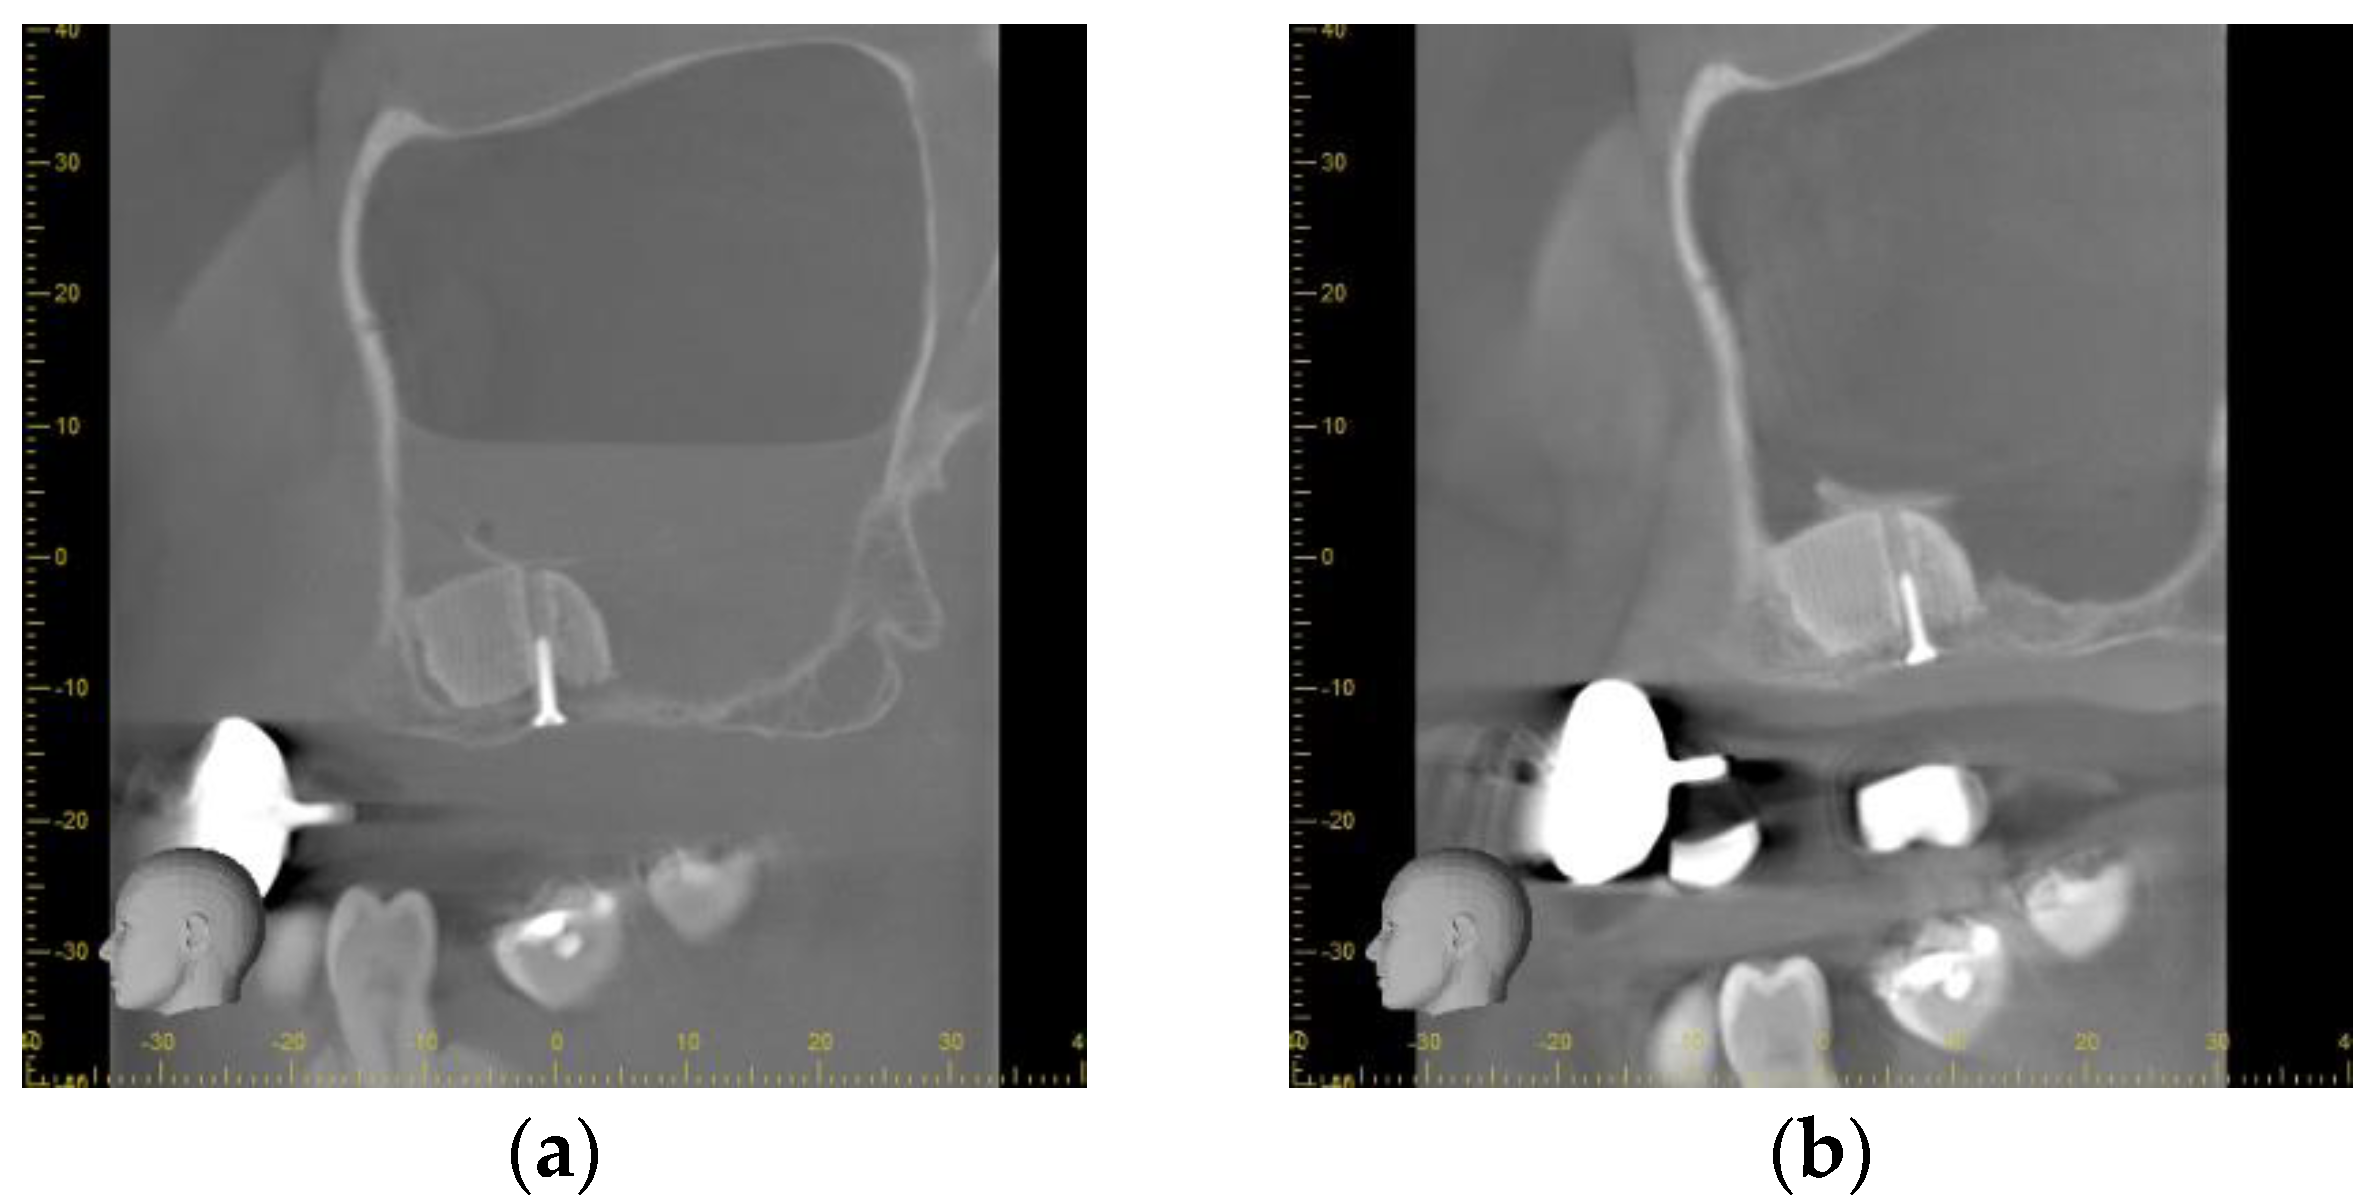

3.2. Radiographical Outcome